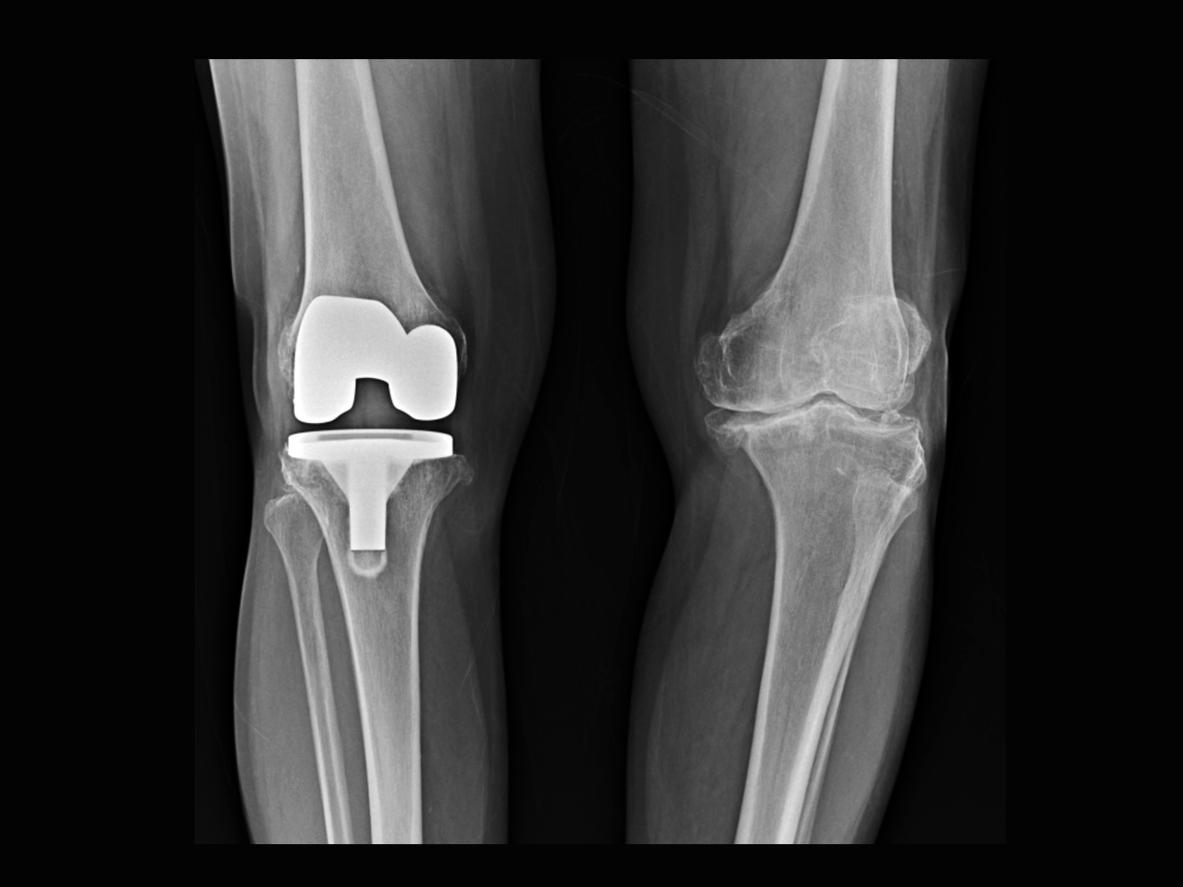

Une opération chirurgicale pour mettre une prothèse du genou peut être proposée aux personnes souffrant d’arthrose mais uniquement si les autres traitements médicamenteux ne fonctionnent pas. Dès lors que la décision est prise, il existe différents types de prothèses, dont celles totales ou unicompartimentales - quand un seul compartiment du genou est touché par l’arthrose-, par exemple. La mise en place de ce type de dispositifs médicaux permet aux patients de retrouver une mobilité de flexion presque complète et une vie quotidienne normale incluant, s’ils le souhaitent, la pratique d’une activité physique. Néanmoins, la reprise sportive doit être progressive en post-opératoire et suivie par un professionnel de santé comme un kinésithérapeute.